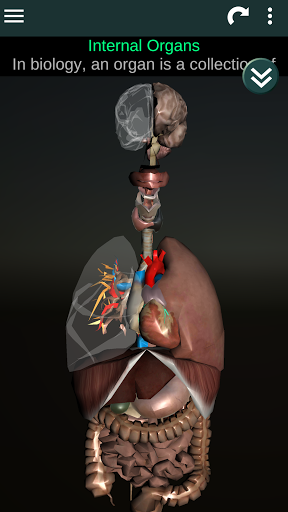

Toont een 3D-anatomisch model van de belangrijkste organen van het menselijk lichaam en een beschrijving van elk orgaan.

Wat zit er in de app?

* Spijsverteringsstelsel, inclusief de maag, dunne darm, dikke darm, en een animatie van dit systeem.

* Ademhalingssysteem, inclusief de luchtpijp, bronchiën, longen en een animatie van dit systeem.

* Voortplantingssysteem, dat de mannelijke en vrouwelijke voortplantingsorganen omvat.

* Hersenen, waaronder de hersenen, het cerebellum en de hersenstam vallen.

* Hart, dat de atria, ventrikels, aorta en een animatie van dit orgel omvat.

* Gemakkelijk te openen en te navigeren (zoom, 3D-rotatie).

* Beschrijvingen van elk orgel.

Deze app is ontworpen als aanvulling op de studie van anatomie in verschillende onderwijs-, gezondheidszorg- en culturele omgevingen.